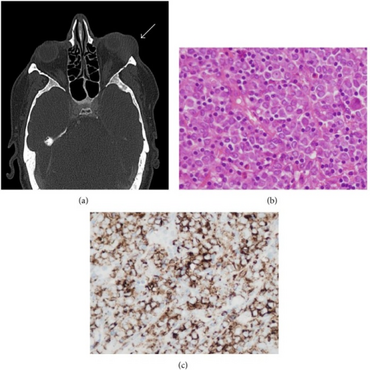

A myeloid sarcoma (chloroma, granulocytic sarcoma,[1]: 744 extramedullary myeloid tumor), is a solid tumor composed of immature white blood cells[2] called myeloblasts. A chloroma is an extramedullary manifestation of acute myeloid leukemia; in other words, it is a solid collection of leukemic cells occurring outside of the bone marrow.

Definitive diagnosis of a chloroma usually requires a biopsy of the lesion in question. Historically, even with a tissue biopsy, pathologic misdiagnosis was an important problem, particularly in patients without a clear pre-existing diagnosis of acute myeloid leukemia to guide the pathologist. In one published series on chloroma, the authors stated that 47% of the patients were initially misdiagnosed, most often as having a malignant lymphoma.[8]

However, with advances in diagnostic techniques, the diagnosis of chloromas can be made more reliable. Traweek et al. described the use of a commercially available panel of monoclonal antibodies, against myeloperoxidase, CD68, CD43, and CD20, to accurately diagnose chloroma via immunohistochemistry and differentiate it from lymphoma.[9] Nowadays, immunohistochemical staining using monoclonal antibodies against CD33 and CD117 would be the mainstay of diagnosis. The increasingly refined use of flow cytometry has also facilitated more accurate diagnosis of these lesions.